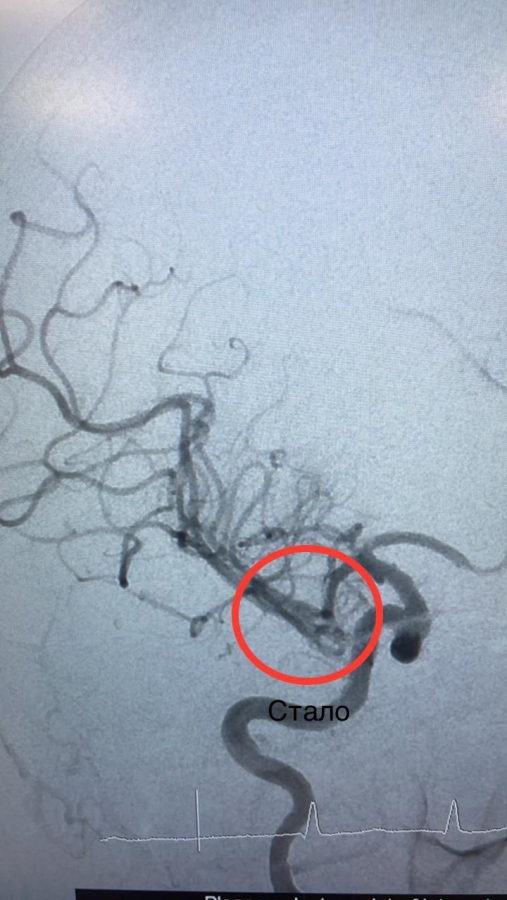

Методы эндоваскулярной окклюзии селезенки: что это и как применяется